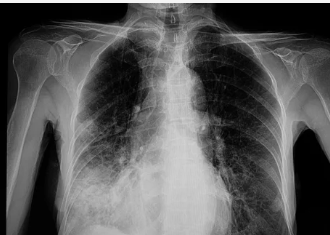

폐렴이 의심될 경우, 병원에서는 다양한 진단 방법을 통해 정확한 상태를 파악합니다.

- 흉부 X-ray: 폐의 염증 상태를 확인하기 위해 가장 기본적으로 시행되는 검사입니다.